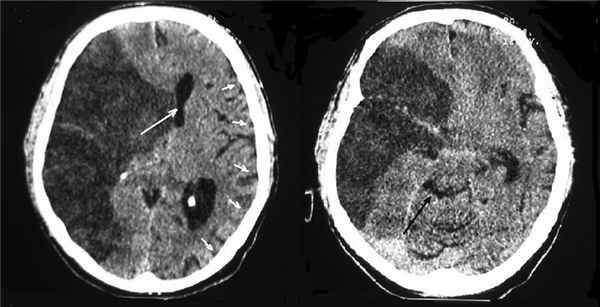

Летальность во 2-й группе составила 52%. В связи с тем что летальный исход у всех больных был обусловлен внечерепными причинами, течение ДС расценивали как благоприятное. У больных не было отмечено поперечной дислокации головного мозга в первые 24 ч от начала заболевания, а при повторной КТ головного мозга в промежуток от 24 до 48 ч от начала заболевания она в среднем составляла 2 мм. На 3-и сутки при повторной КТ латеральная дислокация в среднем достигала 6 мм. У 16 больных при КТ, проведенной на 4-е сутки от дебюта инсульта, латеральная дислокация не нарастала. У этих пациентов динамики уровня бодрствования также не наблюдали. У 7 больных латеральная дислокация продолжила нарастать и на 5-е сутки в среднем достигала 10 мм. У 3 больных с поперечной дислокацией, равной 11, 12 и 15 мм было отмечено угнетение уровня бодрствования до глубокого оглушения. У этих пациентов, несмотря на выраженную поперечную дислокацию, деформация охватывающей цистерны не превышала 1-й степени по классификации В.Н. Корниенко, отека интактного полушария не было (рис. 5). На 6-е сутки от дебюта инсульта по данным КТ латеральная дислокация не увеличивалась и не нарастала аксиальная дислокация. У больных отмечали восстановление уровня бодрствования до ясного сознания в среднем через 5 сут, на 11-е сутки от развития инсульта. В итоге все больные 2-й группы пережили ДС, а угнетение уровня бодрствования до оглушения как проявление субкомпенсации ДС наблюдалось только у 3 (13%) больных, у которых он оказался обратим при проведении консервативного лечения. Средние значения поперечной дислокации во 2-й группе составили 8 мм (4—15 мм), однако ни у одного больного поперечная дислокация не превышала 2 мм в первые 24 ч от начала инсульта или 7 мм в первые 48 ч (pp

Рис. 5. КТ головного мозга больного 2-й группы с МИИ с благоприятным течением ДС (5-е сутки от начала заболевания, уровень бодрствования соответствует оглушению). Отмечается смещение срединных структур влево на 15 мм (белая стрелка). Отека левого полушария нет, конвекситальные субарахноидальные борозды не изменены (указаны малыми белыми стрелками), видна деформация охватывающей цистерны 1-й степени по классификации В.Н. Корниенко (черная стрелка).